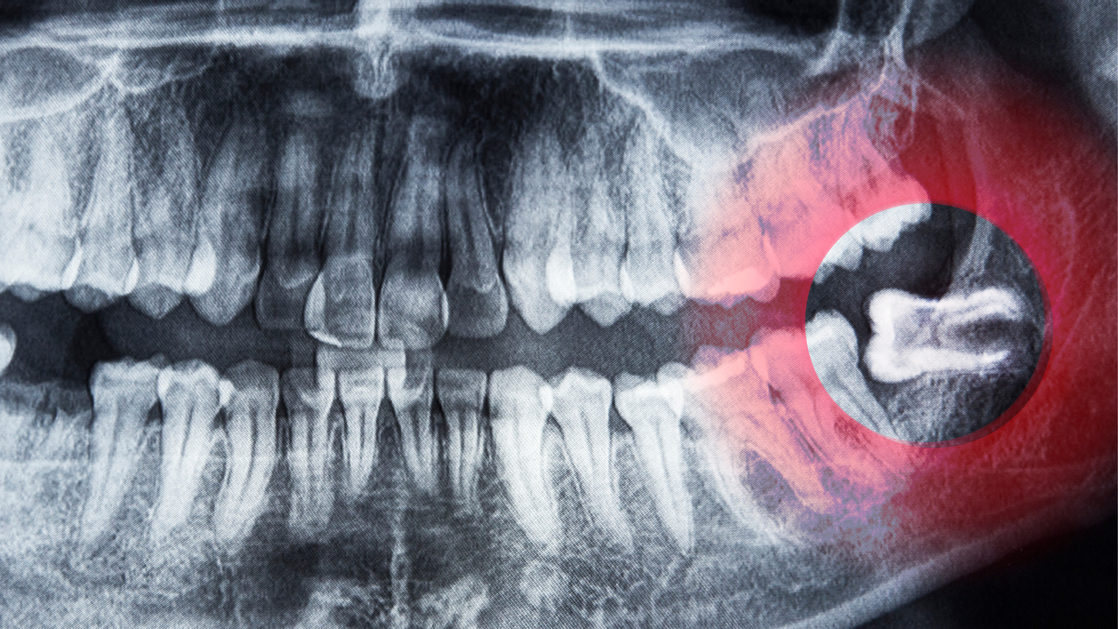

Безболезненное удаление зубов мудрости

Зубы мудрости часто становятся источником дискомфорта: они могут расти неправильно, вызывать воспаление десен или смещение соседних зубов. В клинике Sante мы создали все условия для безопасного и безболезненного удаления зубов мудрости.

• Современная диагностика — КЛКТ 3D‑снимки позволяют точно оценить положение зуба и выбрать оптимальную тактику удаления

• Опытные хирурги — специалисты клиники владеют современными методиками, включая сложные случаи удаления ретинированных зубов